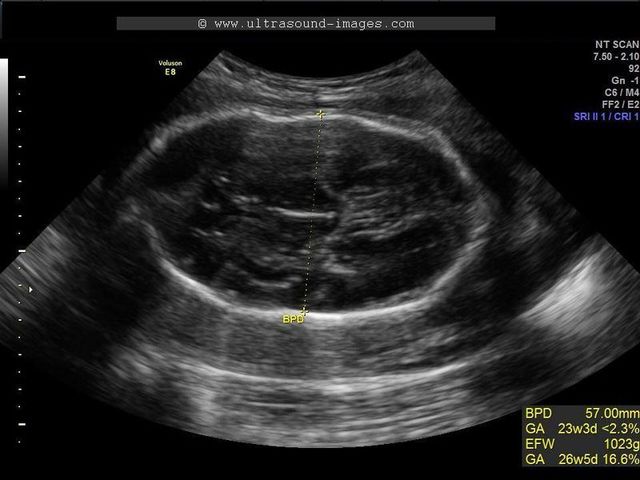

• Fetal Ultrasound

Fetal Ultrasound

Dr. Edward Hon of Yale reported using a Doppler monitor on a woman's abdomen to detect fetal heartbeat. Ultrasound's principles had been known for more than a century (a Swedish physicist, Christian Andreas Doppler, gave his name to the phenomenon in 1842), but this was its first use in prenatal care.